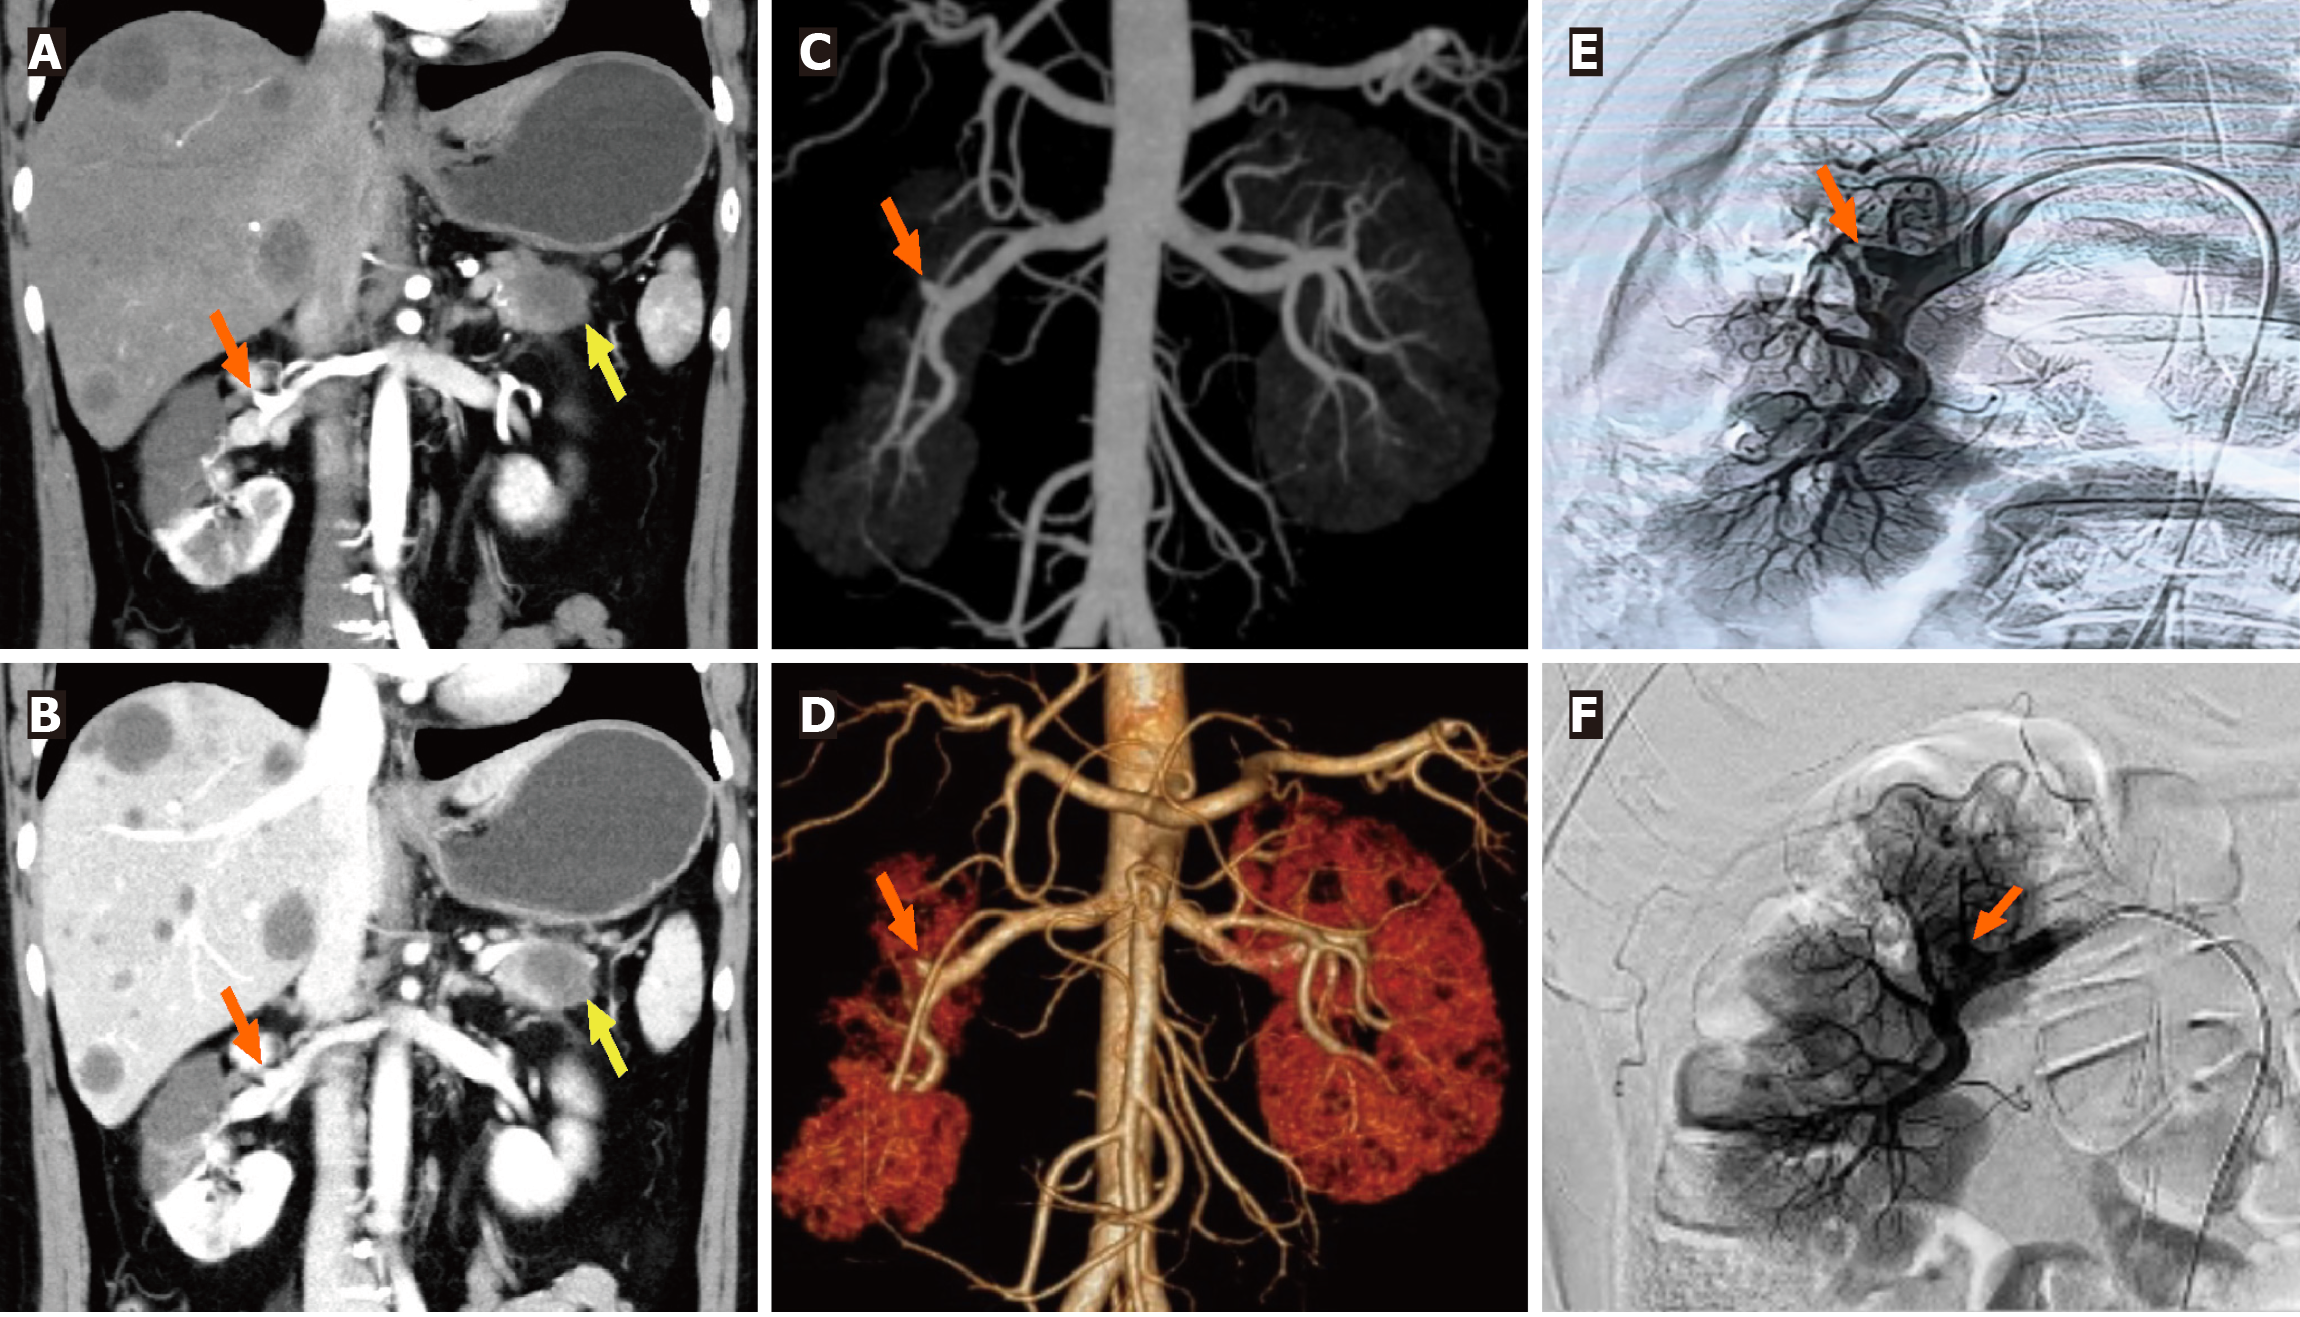

Combined with the discrepancy between the self-symptom and objective signs, we speculated on the possibility of thrombotic diseases and performed total abdominal CT angiography (CTA) and enhanced CT. The mesenteric artery CTA scan showed no significant abnormalities. However, a filling defect was visible in the anterior branch of the right renal artery, suggesting embolus formation, and the right kidney was abnormally enhanced (Figures 1A and 2A-D). Therefore, right renal infarction was diagnosed. Meanwhile, the abdominal CT suggested a soft tissue mass, approximately 4.0 cm × 2.6 cm in size, at the pancreatic tail with a poorly defined boundary, uneven internal density and liquefaction necrosis. On the enhanced scan, the lesion showed mild uneven enhancement, with a slightly high-density shadow in the sur

Right renal artery angiography was promptly performed. Under high-pressure angiography, the blood flow in the upper and middle branches of the right renal artery was occluded, while the lower branch was well visualized (Figure 2E). Subsequently, intravascular thrombolysis with urokinase was administered. An indwelling contrast catheter was placed postoperatively to allow for intermittent infusion of urokinase and standard heparin over 24 hours. The patient reported relief from abdominal pain (Figure 2F). Following this, we transitioned to subcutaneous administration of low-molecular-weight heparin for anticoagulation. Rechecked D-dimer level was 5.79 mg/L.